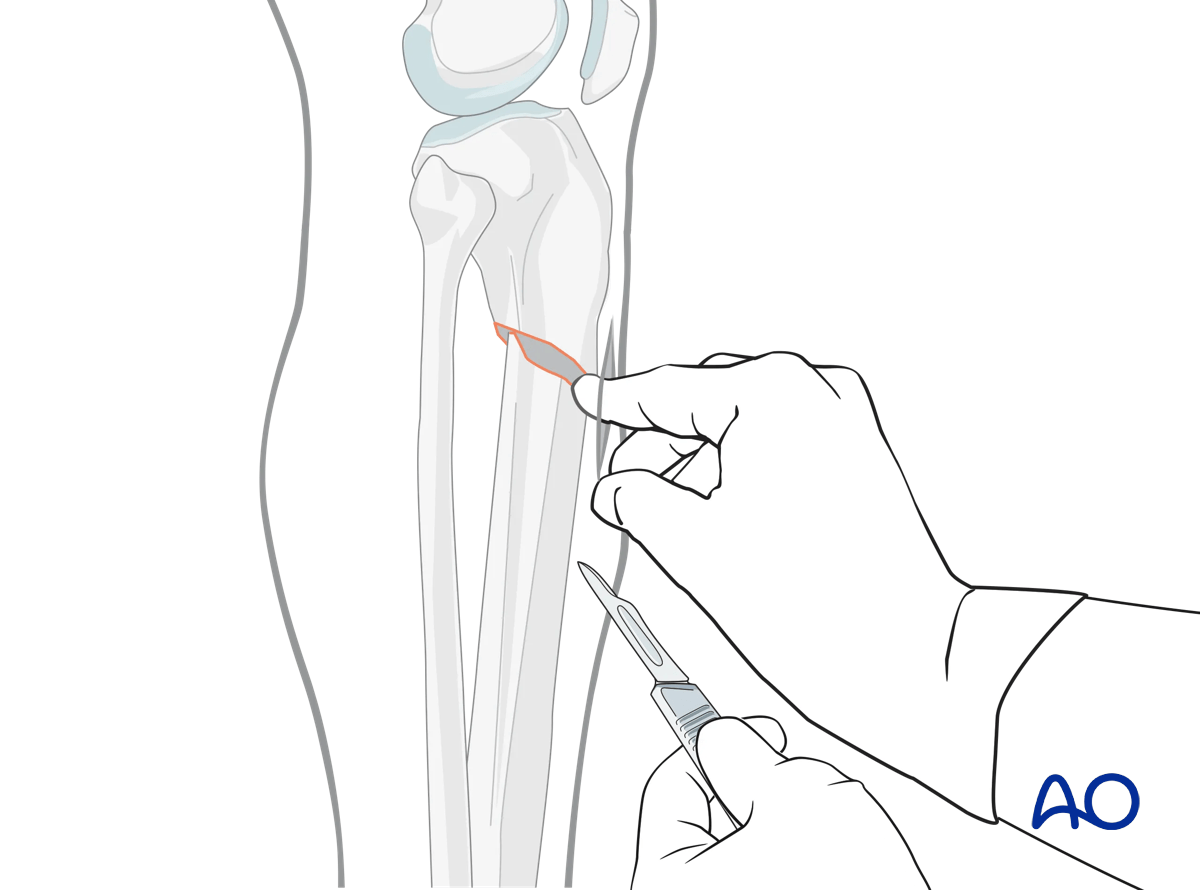

Distal locking - incision

With the leg and fluoroscope properly positioned, an incision is made with radiographic guidance over the selected locking hole. Then the soft tissues are bluntly spread.

Suprapatellar intramedullary nailing, Distal interlocking with fluoroscopic guidance